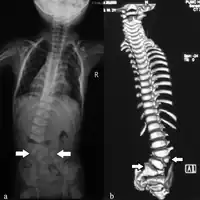

Spine

Vertebral anomalies, or defects of the spinal column, usually consist of small (hypoplastic) vertebrae or hemivertebra where only one half of the bone is formed. About 80 percent of patients with VACTERL association will have vertebral anomalies.[6] In early life these rarely cause any difficulties, although the presence of these defects on a chest x-ray may alert the physician to other defects associated with VACTERL. Later in life these spinal column abnormalities may put the child at risk for developing scoliosis, or curvature of the spine.